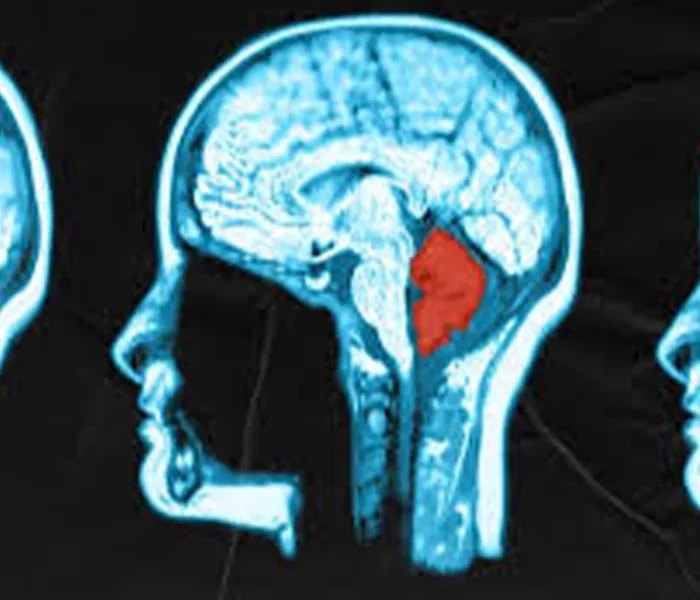

تومور مغزی

جراحی تومور مخچه | راهنمای کامل علائم، روش‌ها و مراقبت‌ها

تومورهای مخچه اگرچه در مقایسه با دیگر انواع تومورهای مغزی شیوع کمتری دارند، اما به دلیل قرار گرفتن در ناحیه‌ای بسیار حساس از مغز، می‌توانند اثرات جدی بر زندگی فرد داشته باشند. مخچه مسئول هماهنگی حرکات بدن، حفظ تعادل و کنترل برخی عملکردهای حیاتی است. بنابراین هرگونه توده یا رشد غیرطبیعی در این ناحیه می‌تواند مشکلات مهمی مانند اختلال در تعادل، دوبینی، مشکلات گفتاری و حتی اختلال در بلع ایجاد کند.

تومور مخچه به رشد غیرطبیعی سلول‌ها در بخش پشتی و پایینی مغز (مخچه) گفته می‌شود. این تومورها ممکن است خوش‌خیم یا بدخیم باشند و بسته به اندازه و محل دقیق رشد، علائم متفاوتی ایجاد کنند.

در کودکان، تومورهایی مانند مدولوبلاستوما شایع‌ترند، در حالی‌که در بزرگسالان بیشتر با همانژیوبلاستوم یا آستروسیتوم مواجه می‌شویم. تشخیص دقیق معمولاً از طریق MRI و در برخی موارد با نمونه‌برداری (بیوپسی) انجام می‌شود.